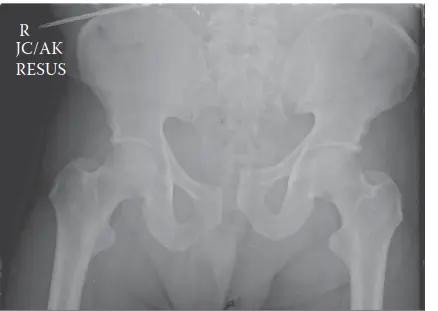

الأشعة السينية الأولية (Initial Trauma Radiographs):

- صورة الحوض الأمامية الخلفية (AP Pelvis): تظهر هذه الصورة أي تباعد في الارتفاق العاني (مفصل العانة الأمامي) أو توسع في المفاصل العجزية الحرقفية، وكسور العجز أو الحرقفة. في حالة المريض محل دراستنا، أظهرت تباعداً كبيراً في الارتفاق العاني (>2.5 سم)، وتوسعاً في المفصل العجزي الحرقفي الأيمن، وكسراً مفتتاً في العجز الأيمن يمتد إلى القناة العصبية (Denis Zone II)، مما يؤكد إصابة حلقة الحوض غير المستقرة.

- صورة المدخل (Inlet View): تُظهر أي إزاحة خلفية أو دوران داخلي لأحد نصفي الحوض.

- صورة المخرج (Outlet View): تكشف عن أي إزاحة عمودية (للأعلى أو للأسفل) لأحد نصفي الحوض، مما يؤكد وجود مكون القص العمودي.

شكل 1: صورة شعاعية أمامية خلفية للحوض تظهر تباعداً كبيراً في الارتفاق العاني، وتوسعاً في المفصل العجزي الحرقفي الأيمن، وتفتتاً في الجناح العجزي الأيمن، مما يدل على إصابة غير مستقرة في حلقة الحوض. -